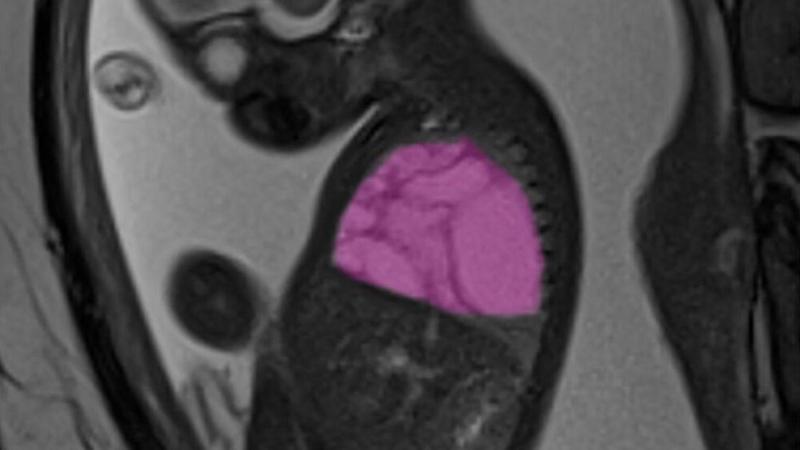

cronaca Una cisti polmonare grande come quasi tutto il torace metteva a rischio la vita del piccolo Alessandro (nome di fantasia) già prima della...